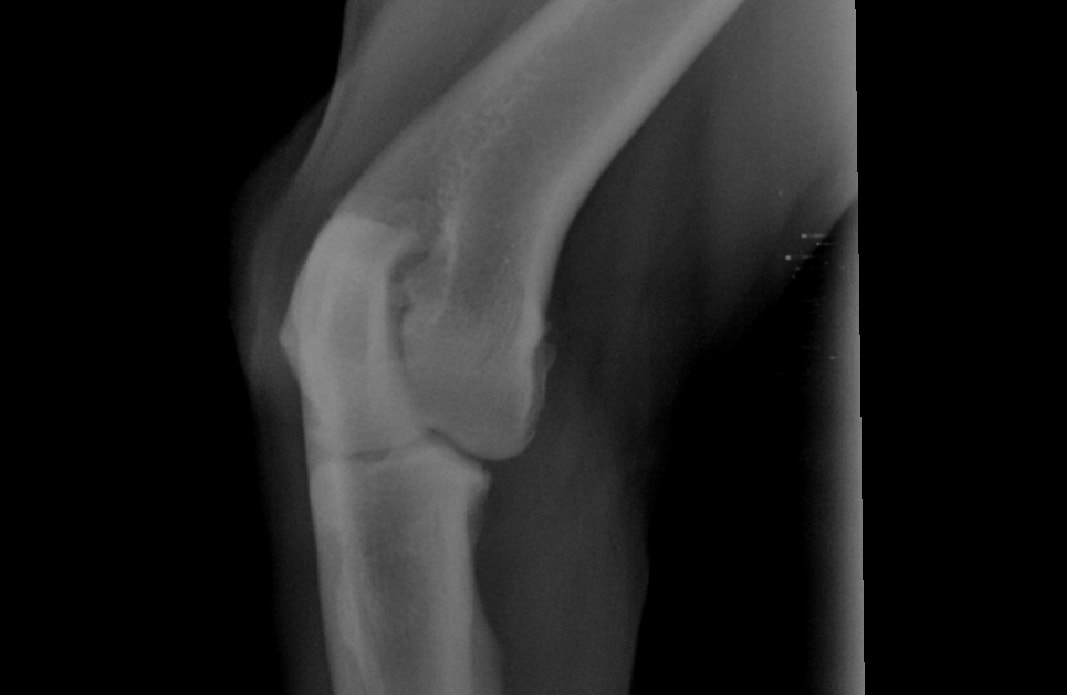

Hi, My Rottweiler is 4 years old. 10 days ago he starting experiencing excruciating pain in is right front leg. we took him to the vet where they took XRays and said he has some inflammation and looks like arthritis. They didn't do much and put him on anti inflams. its been 10 days and made no difference. I have the Xrays attached. Please help so that I know where to send him for proper help.

Hello, sorry to hear about Baloo. His elbows definitely show signs of arthritis. Elbow arthritis is common in Rottweilers has 3 components to it. 2 of these components, a fragments coranoid process and an ununited anconeal process can cause moderate to severe pain. The therapy for this disease includes surgery to remove the chipped bone fragments in the joint. You should consult with an orthopedic surgeon regarding Baloos elbow disease so that his problem can be addressed. In the mean time, you can ask your veterinarian for additional pain meds to try and help keep Baloo as comfortable as possible. Hope this helps and best of luck